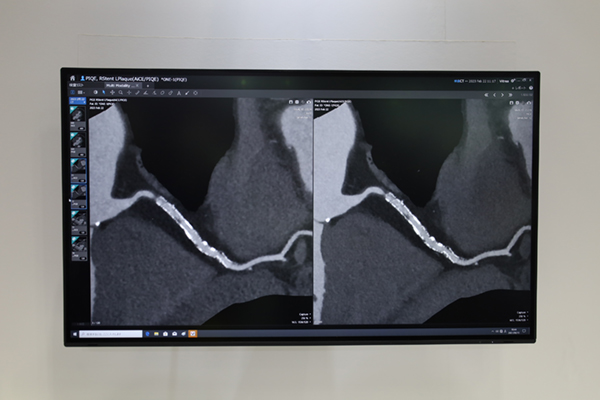

CTでは,80列マルチスライスCT「Aquilion Serve」と高精細CT「Aquilion Precision」を実機展示し,高精細とAIを用いた自動化技術を軸に展示を行った。Aquilion Serveでは,ガントリ内のカメラを利用したポジショニングサポート機能の「Automatic Camera Positioning」,低線量で撮影された三次元データを利用して撮影範囲の自動設定を行う「Automatic Scan Planning」,表示させるレイアウトをプリセットできる「Automatic Hanging Layout」など検査をサポートする機能を搭載しているが,これらの機能を新たに「INSTINX」のブランド名で統合した。INSTINXは,世界中の医療機関で行われた臨床テストを元にワークフローの細部にまで改良を加えて,直感的な操作性を実現し効率性と一貫性を追求する新たなワークフローである。また,Aquilion Precisionでは,AiCEのパラメータに脳血管用(Brain CTA),中内耳用(Inner Ear),骨・軟部用(Bone)が加わり,AiCEが全身領域に適応可能になったことを紹介した。さらにADCT「Aquilion ONE / PRISM Edition」に搭載された超解像技術「Precise IQ Engine(PIQE)」については,微小石灰化プラークや冠動脈ステントの描出など心臓CT領域で高精細画像が得られることを多くの臨床データでアピールした。

超解像DLRのPIQEによりADCTで撮影した冠動脈ステントの描出能が向上